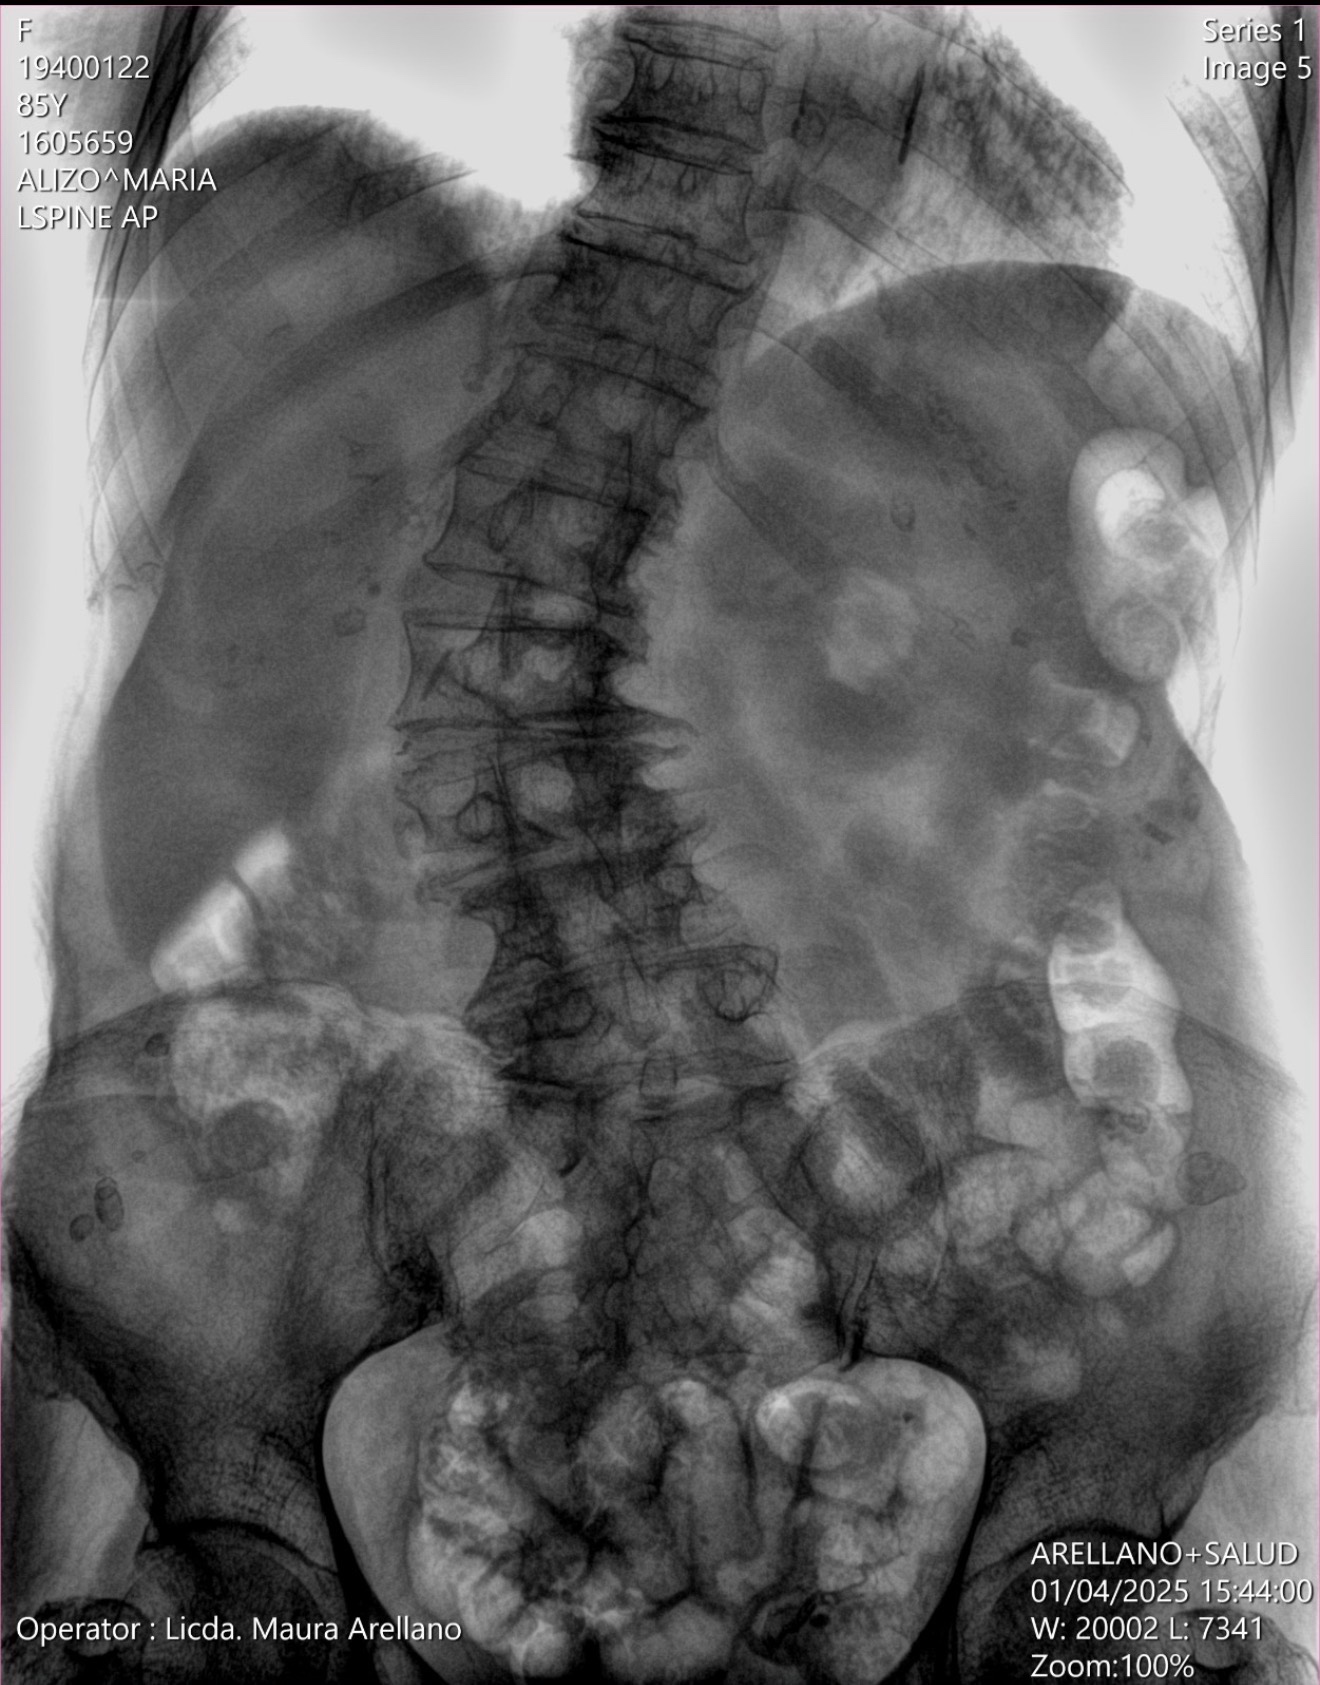

For several years, she has suffered from chronic lower back pain of moderate to severe intensity. The pain now radiates down her right leg and has progressively worsened. She is also experiencing muscle weakness in her right leg and numbness and tingling in both legs. Over the past six months, her condition has significantly deteriorated despite medical treatment.

After medical evaluation and imaging studies, her doctors have determined that surgery is now necessary. Without this procedure, her mobility and quality of life will continue to decline.